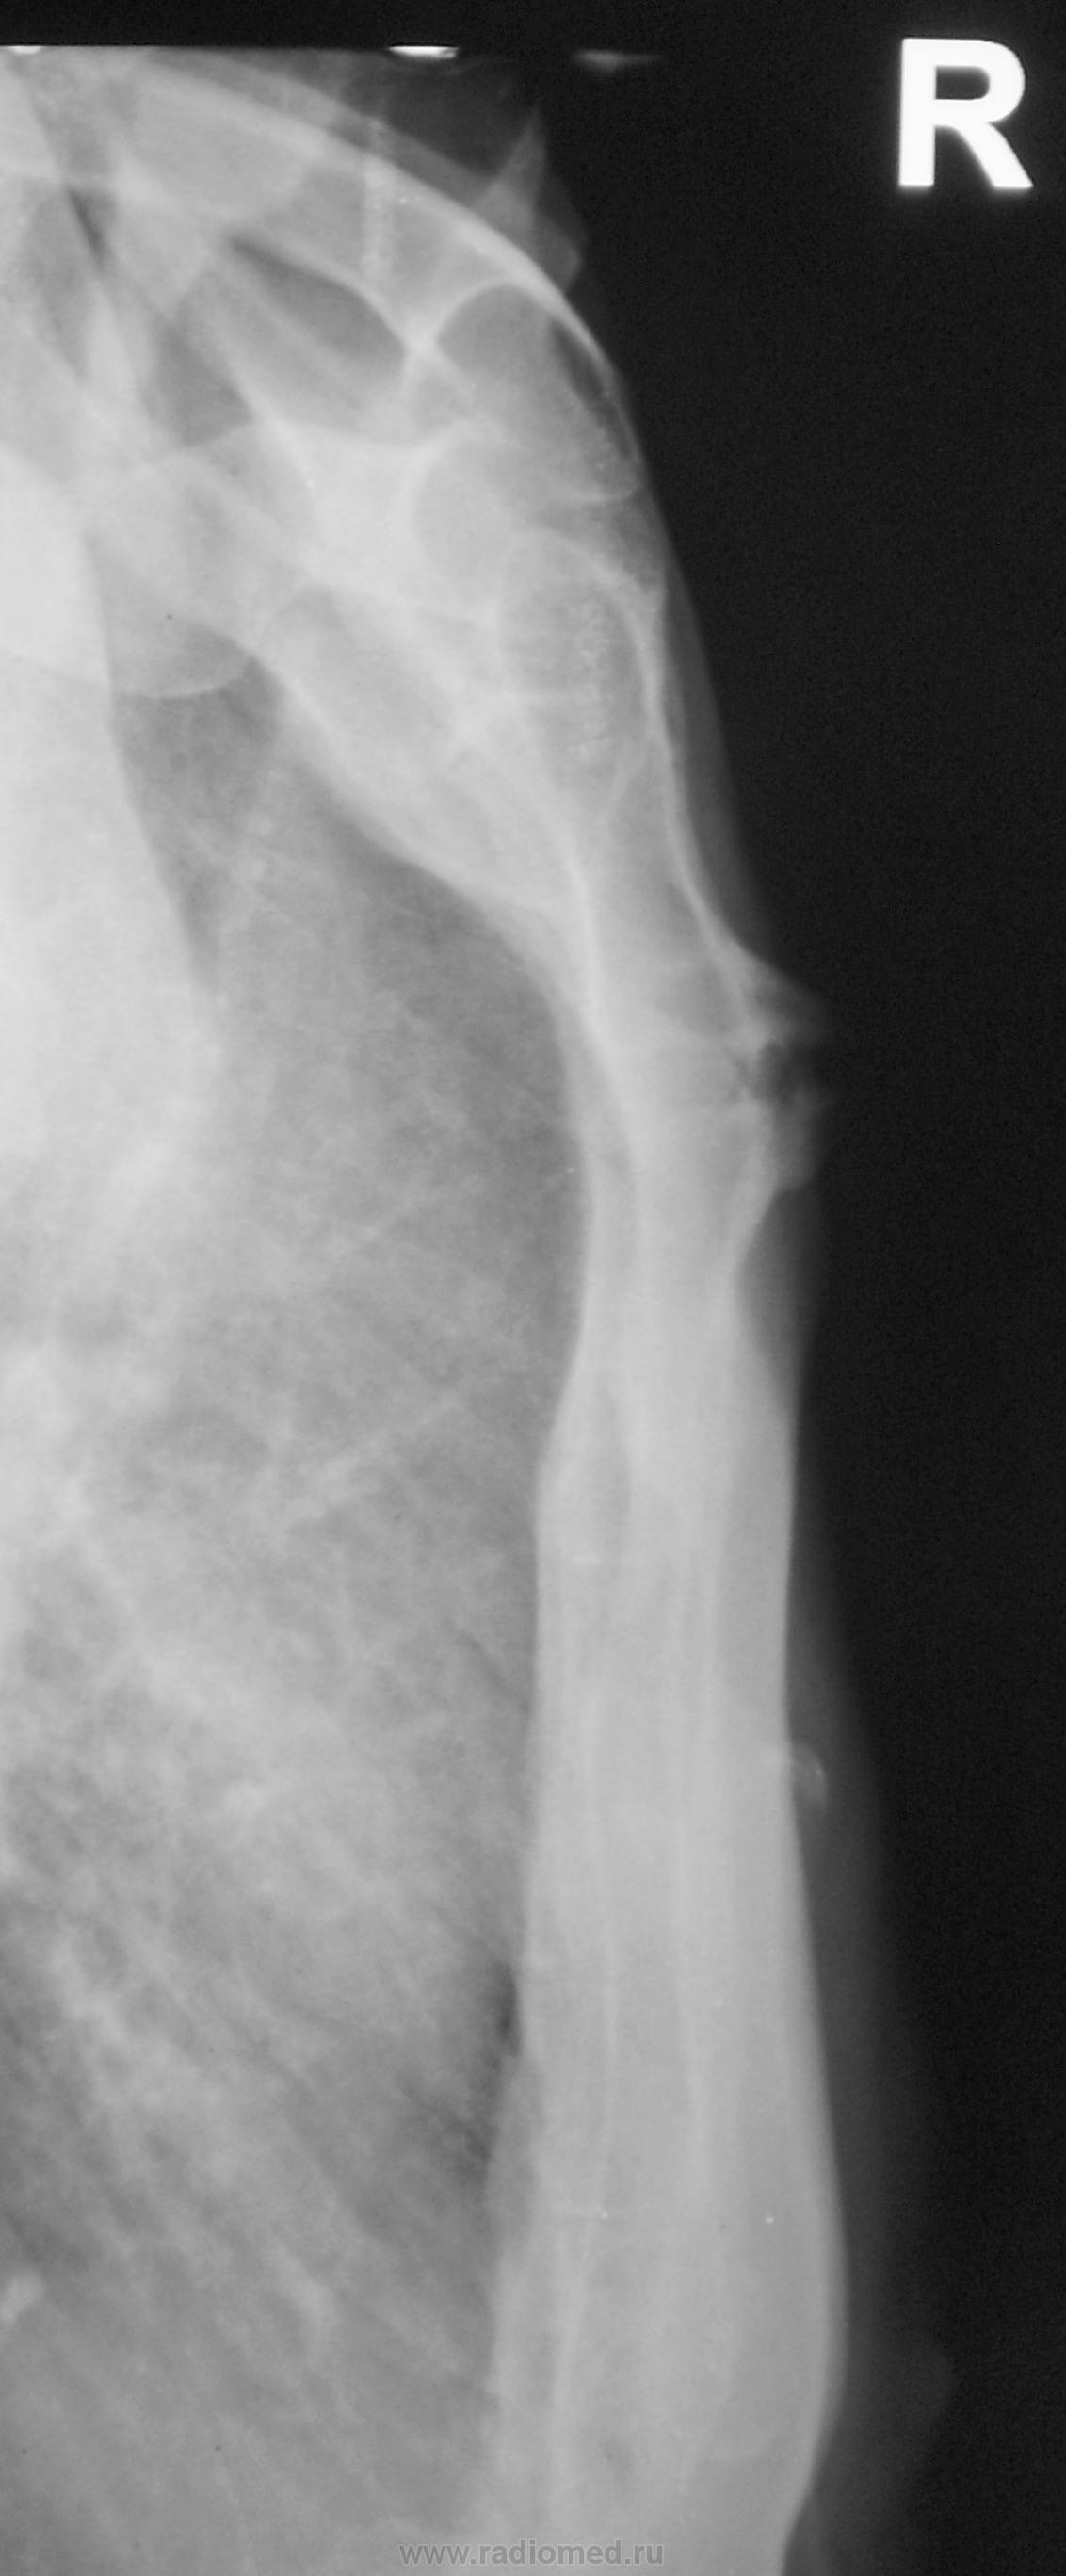

Снимки хорошие, но всё-таки сделал бы томографию. А так, скорее всего, признаки артроза в суставе между телом и рукояткой грудины.

Какой-то остеохондрит типа "Титце".

Артроз то - артрозом, но нет ли тут и асептического некроза нижне-внутреннего края рукоятки грудины....или мне секвестроподобная тень в этом участке "мерещится"?))))

Однако, при таких размеров "шишечке" клиника неблагополучия должна быть!